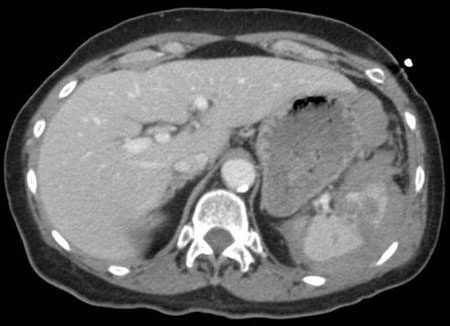

Exploración por TC que muestra laceración esplénica

Colección del MetroHealth Medical Center